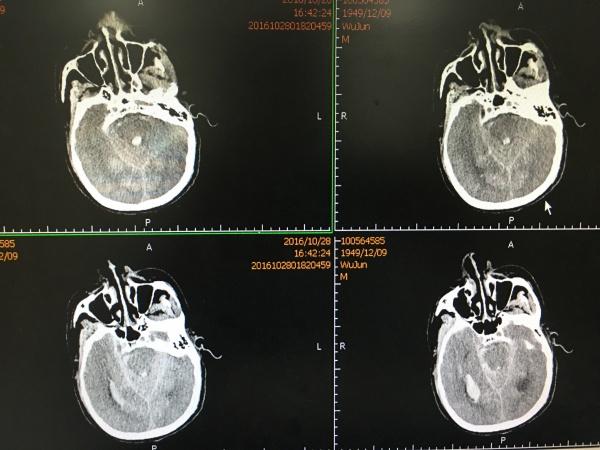

又是一个不珍惜自己的病例! 患者老年男性,半年前因突发头痛于外院就诊,行头颅CTA检查示右侧 Middle celebral artery M2 动脉瘤,因出血量少,患者意识清晰,故未听从医生的建议手术治疗,而是待出血吸收后返家,而且照常通宵打牌、吸烟、喝酒。 终于,上月底,老天给他记了大过: 患者在亲戚家玩麻将时突发头痛、呕吐伴肢体乏力,急送我院,行“头颅CT“示广泛SAH伴右侧侧裂内血肿,患者逐渐出现嗜睡、大小便失禁、呼之不应,急转至我院急诊,行头颅CTA检查示右侧MCA M2段动脉瘤,此时,患者已深昏迷,GCS:4分。

片中示巨大脑内血肿,而且出血破入脑室,右侧侧脑室铸型。